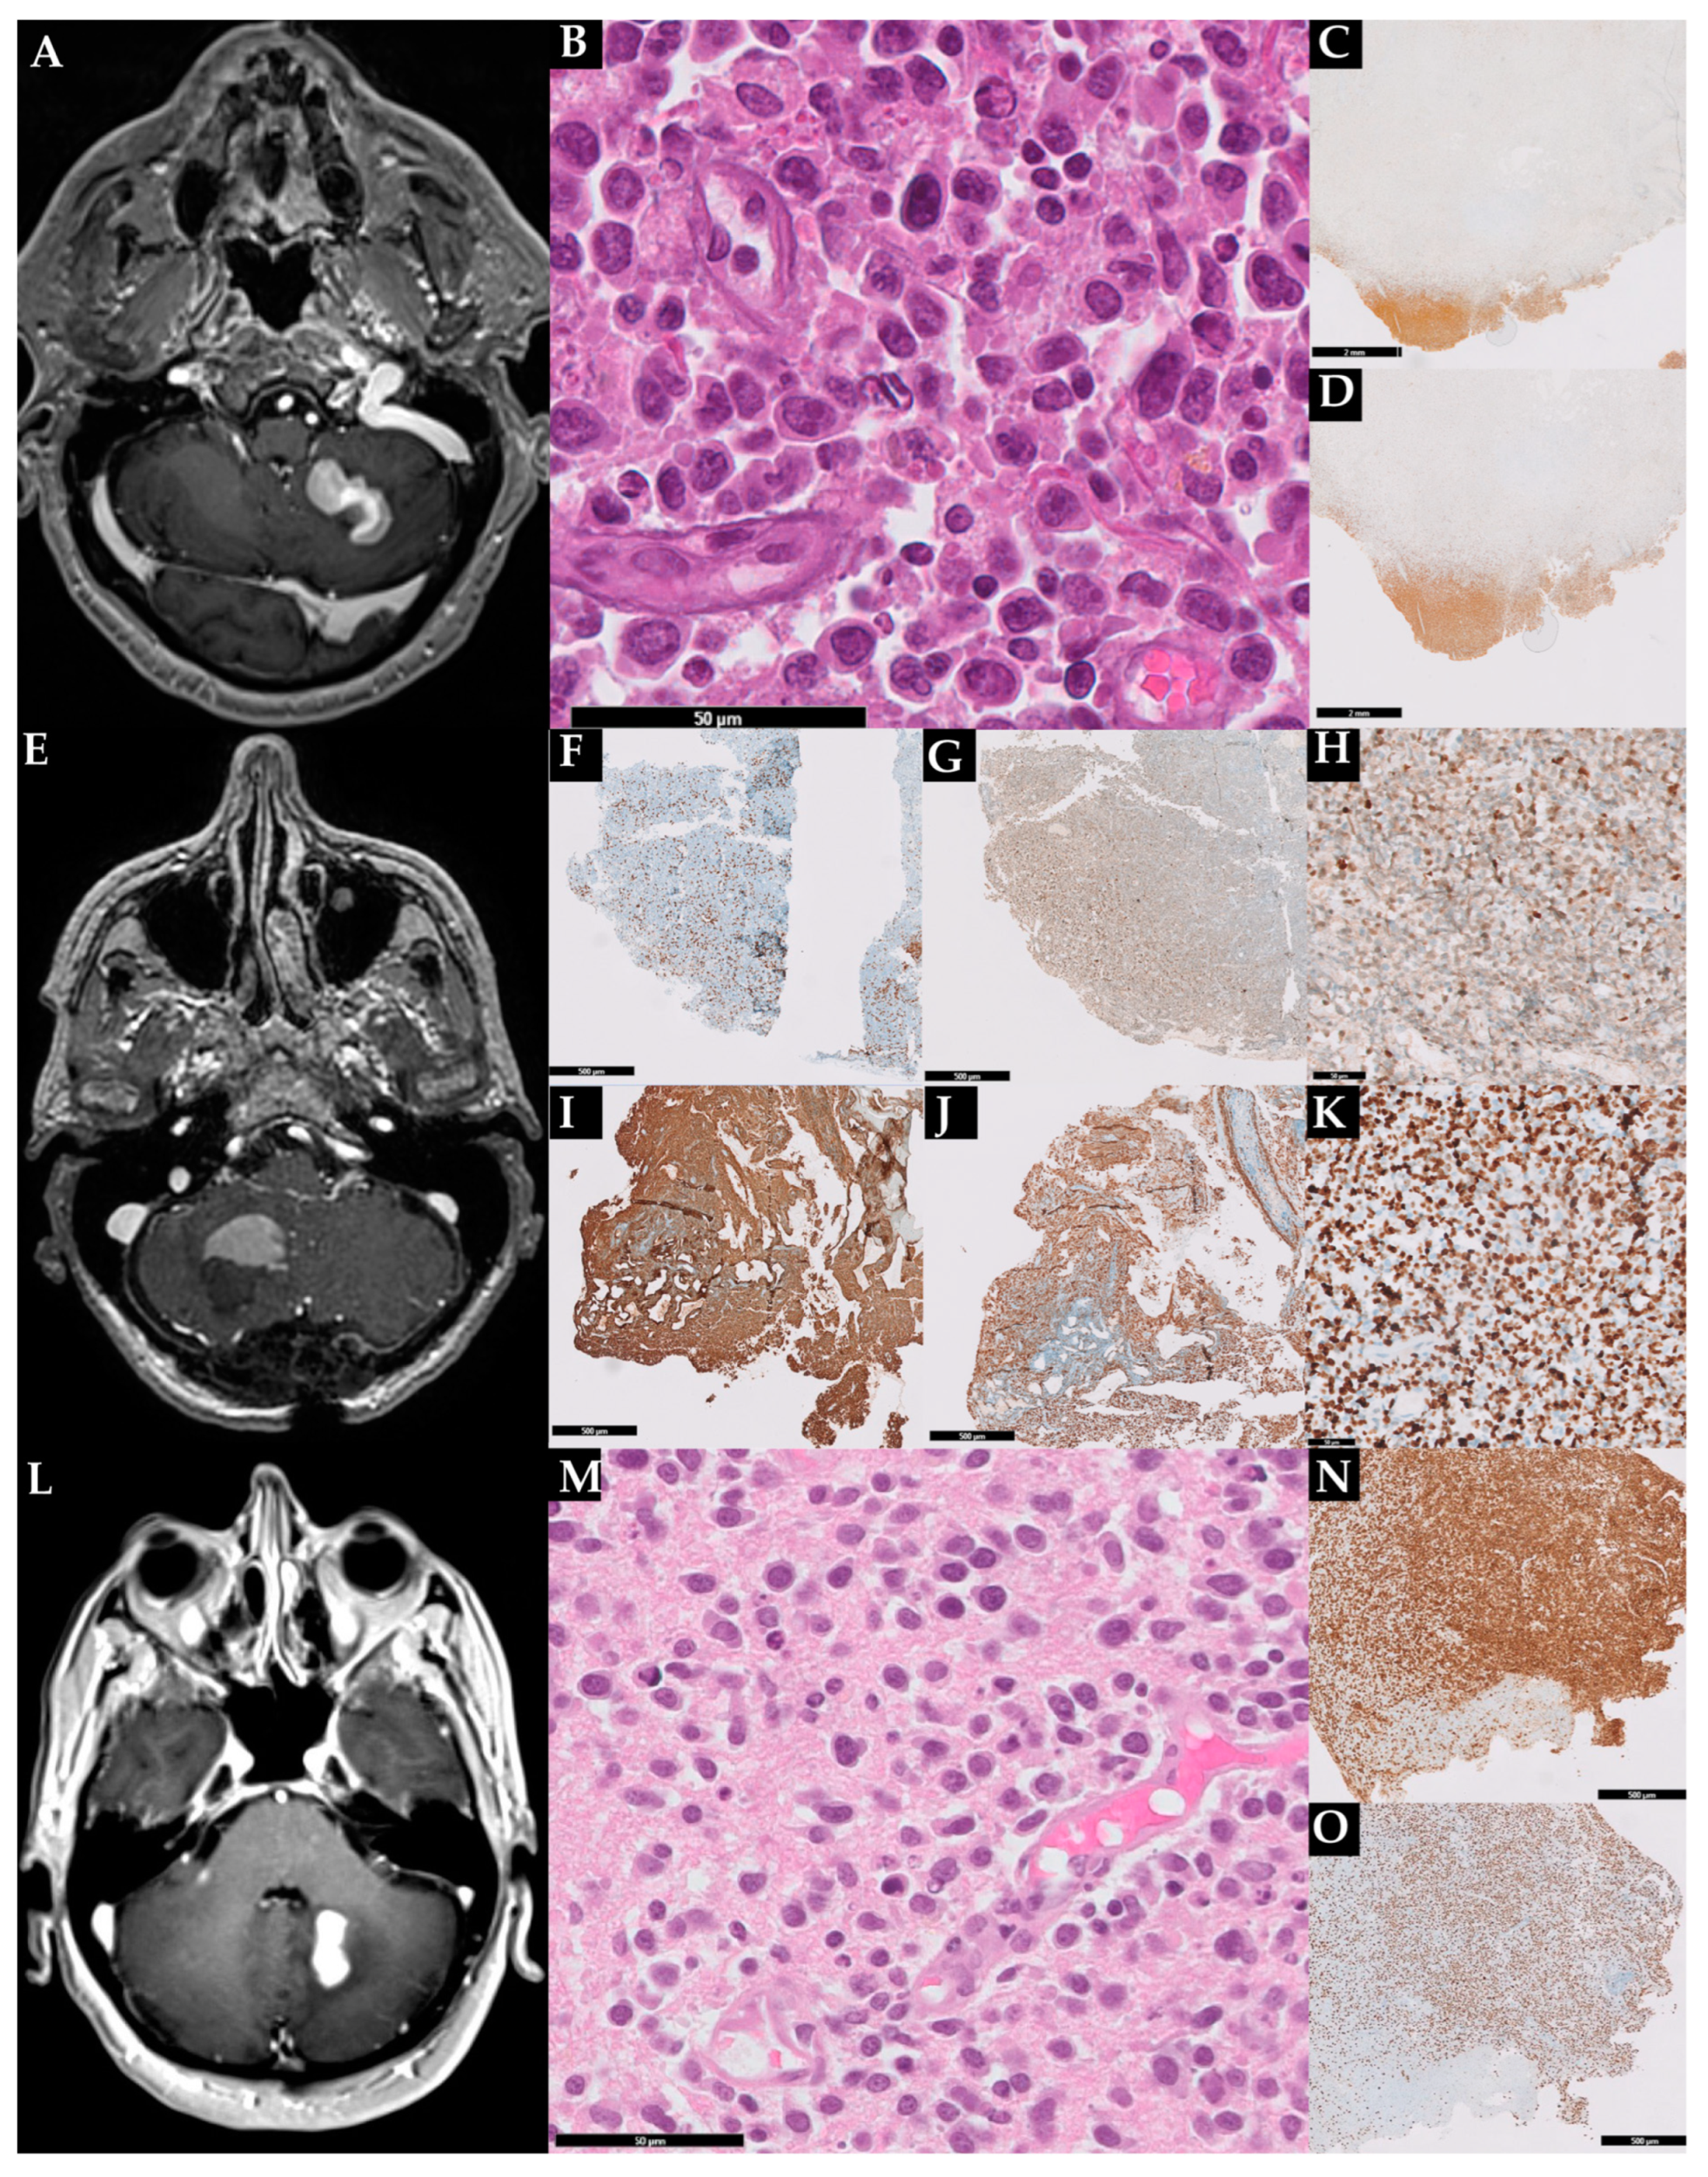

The radiological and histopathological features of our three patients are further depicted in Figure 1 and summarized in Table 1 and Table 2.

Radiological and histopathological features of the three described cases. Case 1: brain MRI showing a mass in the left cerebellar hemisphere (A); hematoxylin and eosin with sheets of large pleomorphic cells (B); immunoreactive for CD20 (C); the lymphoma exhibited a high proliferation index (70%) (D). In (C,D) is also evident a large area of necrosis. Case 2: MRI showing a mass in the right hemisphere (E). Histopathological analisys revealed sparse CD3+ (F) and Bcl2+ (G) T-cells and a B-cell lymphoproliferation expressing MUM1 (H), CD20 (I), and p53 (J); the lymphoma exhibited a high proliferation index (K). Case 3: brain MRI showing a mass in the right cerebellar hemisphere close to the dentate nucleus (L); cerebellar sample staining in HE large lymphoid cells with centralistic morphology and perivascular preservation (M); the lymphoma expressed PAX5 (N) and exhibited a high proliferation index (O).